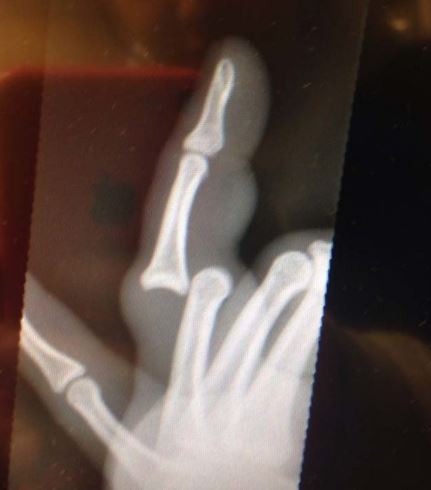

Pokud se vám někdy stal vážnější úraz nebo nehoda, určitě víte jaký to je pocit, když vám musí rentgenovat a prohmatávat zpřeházené nebo popraskané kosti. Ano, není to nic příjemného. Proto tu máme dnes galerii úlovků z rentgenu, které se jen tak nevidí.